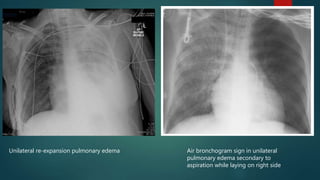

Unilateral re-expansion pulmonary edema Air bronchogram sign in unilateral

pulmonary edema secondary to

aspiration while laying on right side

Unilateral re-expansion pulmonaryedema Air bronchogram sign in unilateral pulmonary edema secondary to aspiration while laying on right side